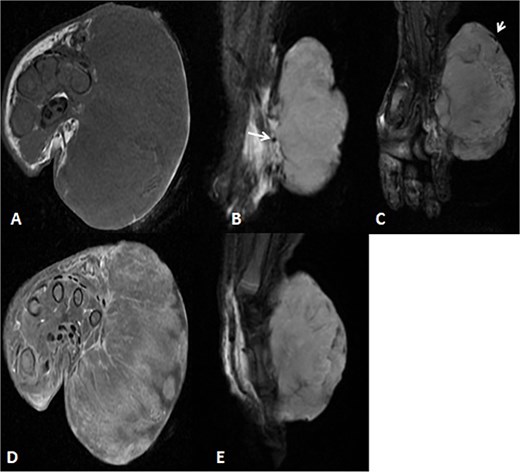

Before the presentation, the patient had an MRI done 3 weeks prior which showed a left thigh quadriceps muscle region mass measuring 3.9 × 4 × 4.7 cm. The mass showed peripheral discontinuous nodular enhancement in the early phase with centripetal enhancement in the delayed phase on postcontrast images, matching the description of a hemangioma (Fig. 2). Upon presentation, a left inguinal US was done, which showed a mass measuring 9.1 × 8.3 × 8.7 cm. The mass appeared heterogeneously isoechoic with areas of cystic changes and showed atypical manifestation on color Doppler. The US was done 3 weeks after the MRI (Fig. 3).

Uploaded MRIs of the left inguinal mass. (A and B) Coronal and axial short tau inversion recovery (STIR) images show a well-defined large heterogeneously high signal intensity with an area of signal void arising from the left upper thigh quadriceps muscles region. (C) Axial T1WI shows that mass appear isointense in signal intensity in correlation to the muscle signal with no intralesional hemorrhagic component. (D and E) Axial T1 fat-saturated images’ early and delayed phases show peripheral discontinuous nodular enhancement with subsequent centripetal enhancement on the delayed phase. The aforementioned MR findings are typical for hemangiomas.